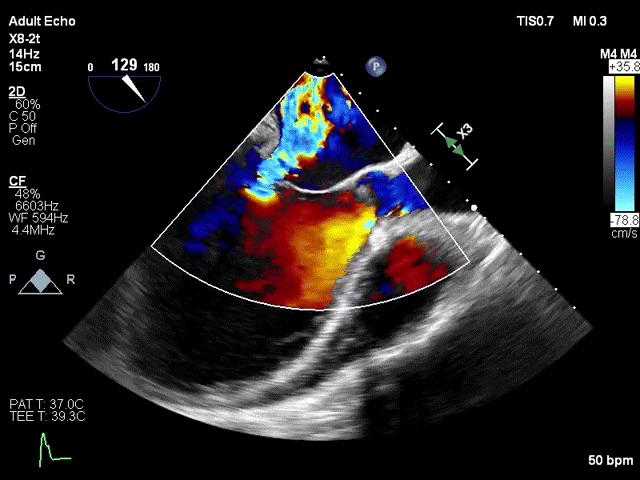

术前超声评估

该手术采用左侧第五肋间微创切口心尖入路,透视下经导丝置入输送系统,逐步释放瓣膜。透视及TEE确认瓣膜位置满意后撤出输送系统,二尖瓣瓣膜形态及工作状态良好,复查左心室造影,提示无瓣周漏,无左室流出道梗阻,左右冠状动脉显示良好,未受任何影响。

患者基线资料

该例患者为57岁男性,因扩张型心肌病合并严重心功能不全,并伴有高尿酸血症、高脂血症等疾病。超声心动图评估提示二尖瓣重度反流、轻微主动脉瓣反流与轻微三尖瓣反流,LVEDD 83mm,LVESD 73mm,LVEF 34%。二尖瓣反流机制为功能性反流,有效反流口面积为0.49cm²,反流量93mL,瓣口面积为6.7cm²。